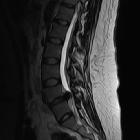

Disc protrusions are a type of disc herniation characterized by protrusion of disc content beyond the normal confines of the intervertebral disc, over a segment less than 25% of the circumference of the disc. The width of the base is wider than the largest diameter of the disc material which projects beyond the normal disc margins. The protrusion must not extend above or below the relevant vertebral endplates .

Disc bulge is distinguished from a disc protrusion in that it involves more than 25% of the circumference.

A disc extrusion is distinguished from a disc protrusion in that the base of the protruded disc material is narrower than its 'dome'. Furthermore, this material may extend above or below the disc level.